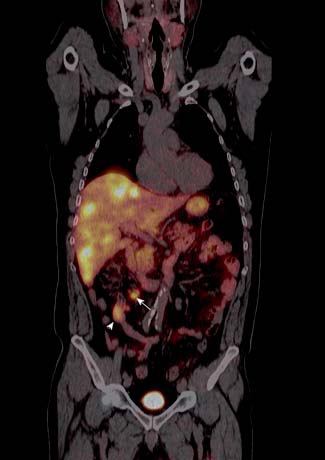

Tumores gastroenteropancreáticos

Este grupo (GEP) constituyen un grupo heterogéneo de tumores neuroendocrinos del estómago, páncreas e intestino. El más frecuente es el tumor carcinoide. El tratamiento primario es la cirugía aún en los pacientes con enfermedad metastásica, debido a que la resección parcial puede mejorar la calidad de vida, sobrevida y estado funcional. Las imágenes cumplen un papel importante para determinar la extensión de la enfermedad al inicio y en el seguimiento. Los estudios realizados con 111In pentatreotide muestran elevada sensibilidad para la detección de GEP a excepción del insulinoma. La sensibilidad para el gastrinoma metastásico, carcinoide y otros GEP son generalmente sobre 80% hasta 94%. La sensibilidad para la enfermedad metastásica tiende a ser superior a la de los tumores primarios (Figura 1) y en muchas ocasiones se encuentran lesiones no detectables por imágenes anatómicas. Utilizando Ga68 análogos de somatostatina se han obtenido excelentes resultados, con sensibilidades entre 82-100% (Figuras 2 y 3). El FDG tiene baja sensibilidad para la detección de estos tumores de lento crecimiento, bien diferenciados y bajo Ki-67, en cambio las imágenes con análogos de somatostatina presentan un patrón opuesto (Figura 4 y 5). Los tumores neuroendocrinos indiferenciados y agresivos presentan marcada avidez por la glucosa y pobre expresión de receptores de somatostatina y viceversa. Se ha visto que los pacientes con tumores con mayor expresión de Ki-67 evolucionan peor que aquellos con bajo Ki-6715. Los tumores neuroendocrinos que captan FDG tienen por lo tanto peor pronóstico16. En un estudio que comparó el rendimiento de cintigrafía con Octreoscan y FDG en pacientes con tumor carcinoide encontró que el 86% de los tumores primarios se localizaban con pentatreotide mientras que sólo el 57% con FDG. Pacientes con metástasis, el 69% fue positivo con el análogo de somatostatina, 47% con FDG y 56% con imágenes anatómicas17. Figuras similares se han obtenido con el uso de PET y Ga68análogos de somatostatina18,19.